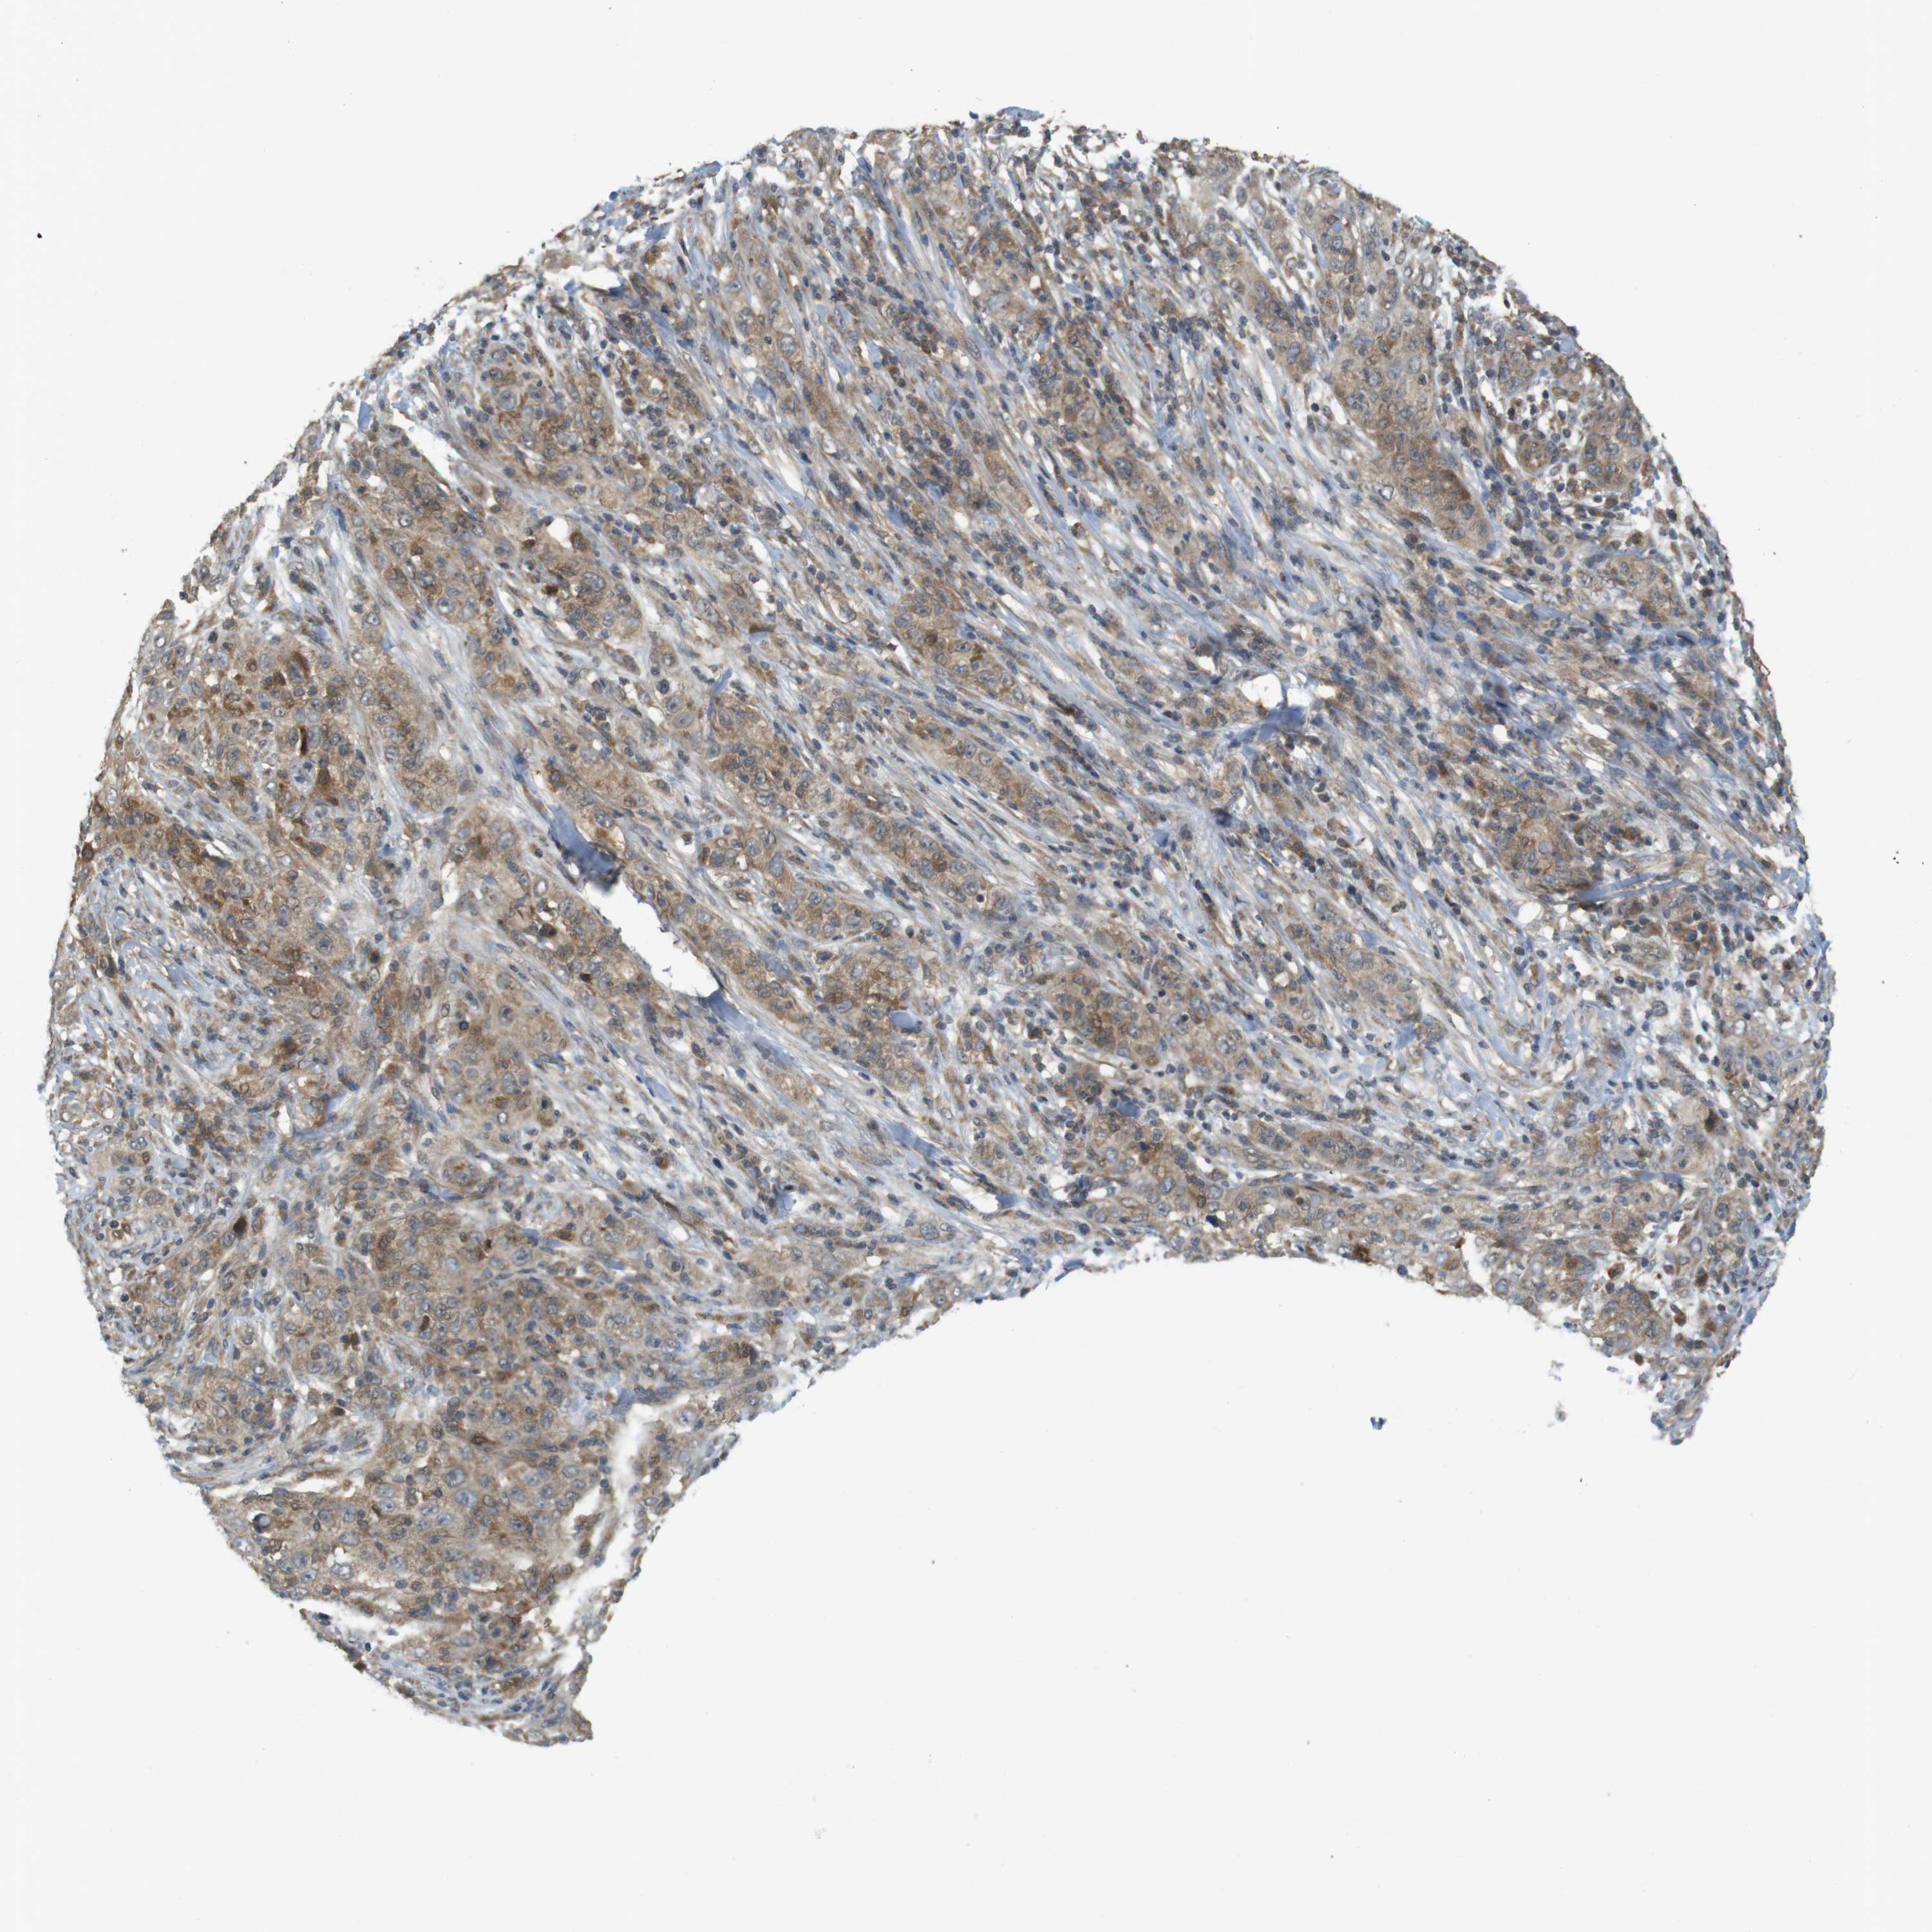

SKIN CANCER

Basal cell and squamous cell cancer